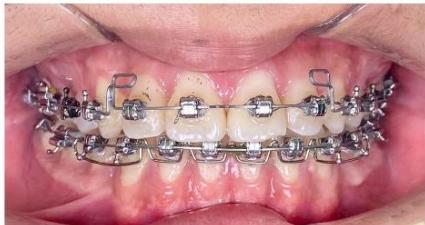

### c) Incisor Retraction using Segmented Mechanics

After completion of canine retraction, the incisor segment was retracted using segmented mechanics according to the Ricketts Bioprogressive philosophy. Retraction arches in both arches were designed to achieve three objectives simultaneously: (i) controlled incisor retraction; (ii) activation of an intrusive component of approximately 2-3 mm to counteract anterior tooth extrusion, which is particularly critical in high-angle patients; and (iii) generation of strong and stable positive torque to achieve three-dimensional control of incisor root movement, especially in the mandibular arch [19-21]. The retraction arches were activated at a rate of approximately 1.5 mm per month while maintaining torque and vertical control.

During the finishing phase, the ART torque spring was continuously maintained in the mandibular incisor region to reduce secondary negative torque and to assist in directing the incisor roots into cancellous bone, thereby protecting the labial cortical plate during the stage when retraction forces generate the most unfavorable moments [22-24].

After the occlusal objectives were achieved, the patient was progressed through finishing archwires (0.016 NiTi; 0.016×0.022 NiTi; 0.017×0.025 NiTi; and 0.017×0.025 stainless steel), in combination with intermaxillary elastics (3/16-inch, 3.5 oz) for midline correction and occlusal settling. Subsequently, space reopening was observed between the maxillary lateral incisors (tooth 2) and canines (tooth 3) bilaterally. A space-closing archwire with L-shaped loops positioned between teeth 2 and 3 was fabricated, and space closure was activated at approximately 1.5 mm per month over a two-month period, resulting in complete space closure. Thereafter, both arches were placed on 0.017×0.025 stainless steel archwires with full-arch elastomeric chains. Intermaxillary elastics were continued to assist in midline correction and to achieve optimal intercuspation.

Figure 9: Re-leveling and alignment phase following anterior space closure of the four incisors